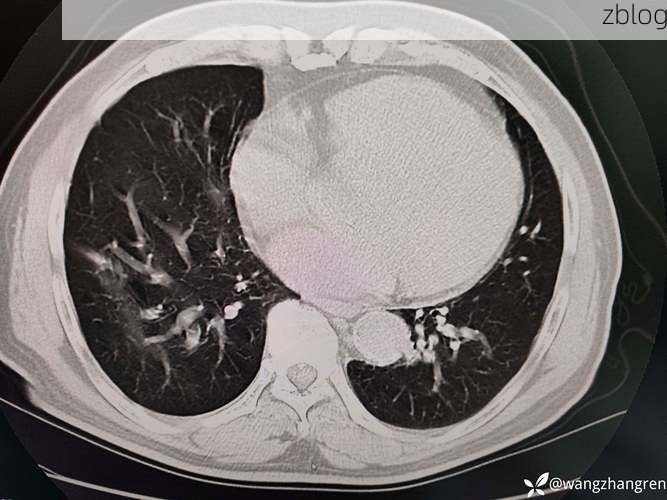

(图片来源网络,侵删)

2022年3月15日,郁南县在对外地返郁人员进行例行核酸检测中,发现1例新冠病毒核酸初筛阳性个案,经市疾控中心复核,确认为新冠肺炎确诊病例(轻型)。该病例已闭环转运至定点医院隔离治疗。